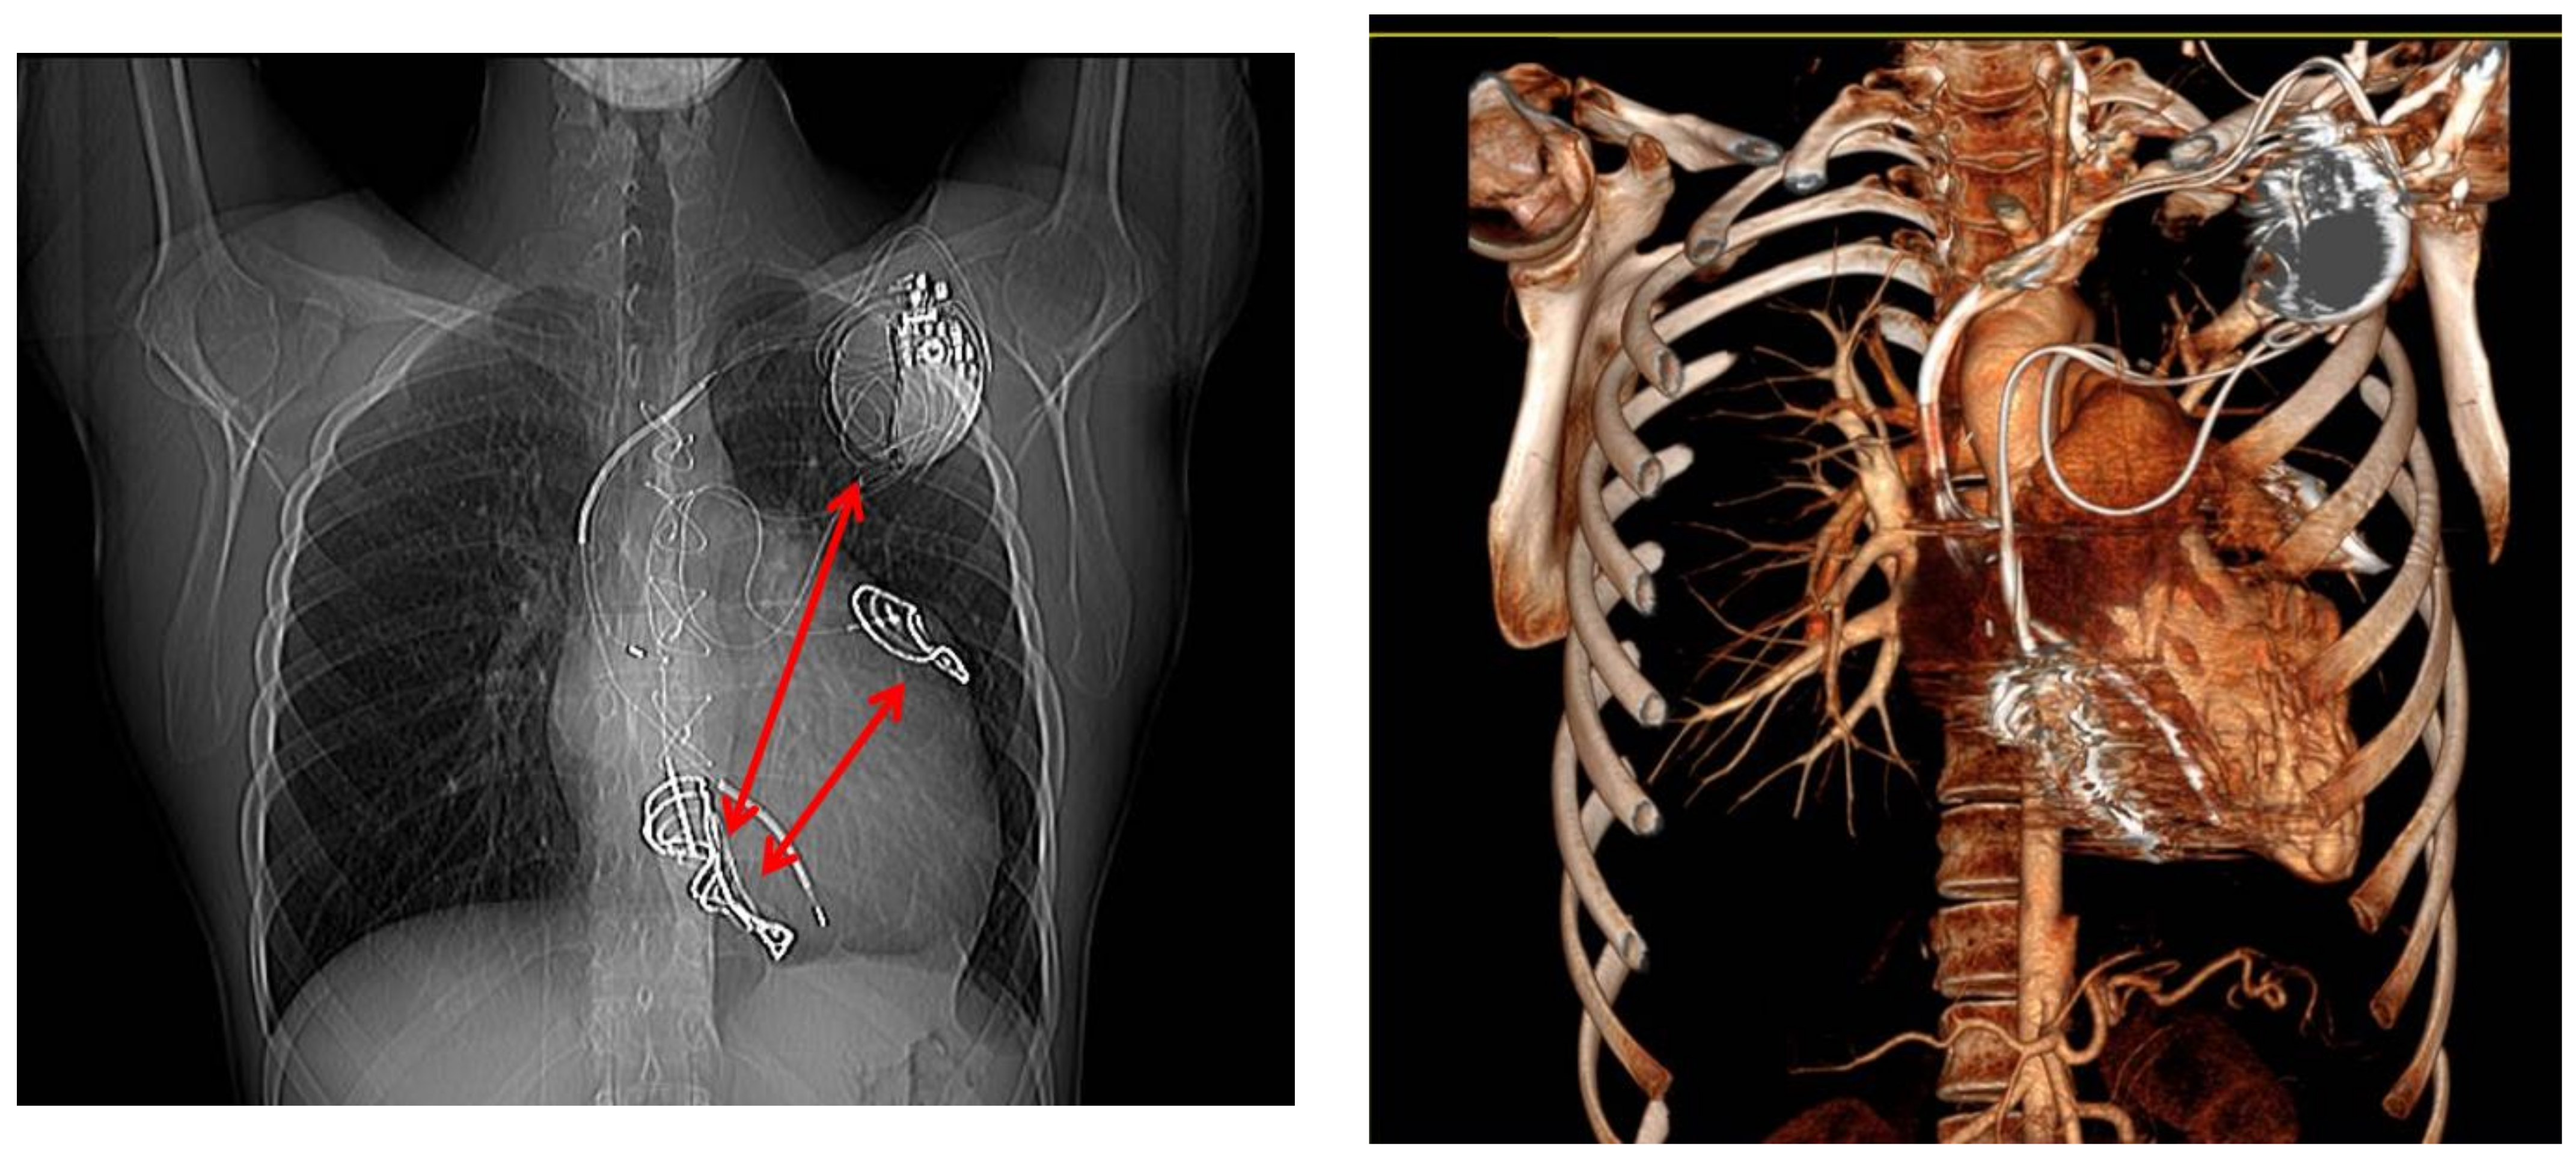

In December 2008, the patient suffered a cardiac arrest due to VF while climbing a flight of stairs. He was successfully resuscitated with external defibrillation and was transported to a local A&E department where he suffered an electric storm with multiple episodes of VF requiring orotracheal intubation. The patient was extubated after 24 hours, had no neurological complications, and underwent a dual-chamber ICD (Teligen, Boston Scientific, Inc., St Paul, MN, USA) implantation with a dual-coil defibrillation ventricular lead. The DFT was ineffective, and the induced VF was externally defibrillated. Subcutaneous multi-coli arrays (Boston Scientific, Inc., St Paul, MN) tunneled into the left postero-lateral position and connected to the superior vena cava (SVC) port of dual-chamber ICD were added to increase the myocardial mass involved in the defibrillation shock pathway (Figure 1). A new DFT was unsuccessful.

Figure 1.

Anterior–posterior (AP) chest X ray showing dual-chamber ICD with a dual-coil defibrillation ventricular lead and subcutaneous multi-coli arrays tunneled into the left postero-lateral position and connected to the SVC port of ICD.